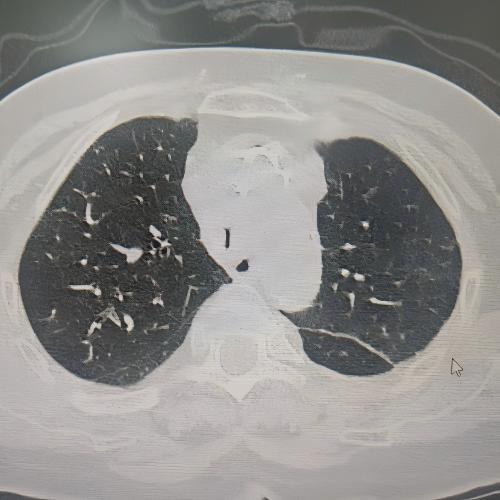

患者为75岁女性,因“反复咳嗽咳痰、气促10余年,加重3月”,于3月3日入住湘雅三医院呼吸与危重症医学科。入院时患者呼吸困难症状严重,CT检查提示气道存在严重狭窄,随时面临窒息风险。经管床医生杨红辉副主任医师评估,患者气管狭窄情况复杂:最狭窄处管腔直径仅剩1-3mm,科室最细的4.0mm支气管镜也无法通过;狭窄位置极低,下缘距隆突仅1.6cm,意味着无法通过气管切开绕过病灶;狭窄处周围组织的CT值高达60-70Hu且无强化,因而直接植入支架存在无法撑开或加重堵塞的风险;同时,患者无法耐受全身麻醉,仅能采用利多卡因进行表面麻醉,操作难度较大。